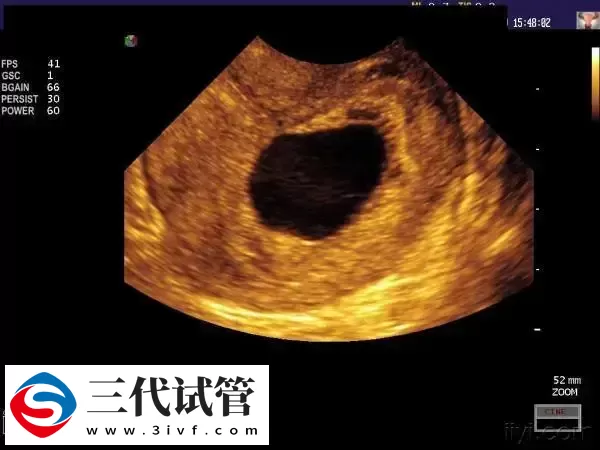

试管婴儿移植后孕囊偏左侧可能是受精卵着床位置偏低、子宫畸形、宫外孕等原因导致的。比如宫腔操作、盆腔感染、宫内绝育器、子宫手术史以及合并子宫畸形、子宫肿瘤等,都可能会使孕囊不能着床于适当的部位,出现这种情况一定要及时去医院治疗。另外建议孕妇定期进行孕检,及时发现问题并采取处理措施。

试管婴儿移植后孕囊偏左侧可能是受精卵着床位置偏低引起的,也可能是子宫畸形、宫外孕等原因导致的。通常可以通过一般治疗、药物治疗、手术治疗的方式进行改善。